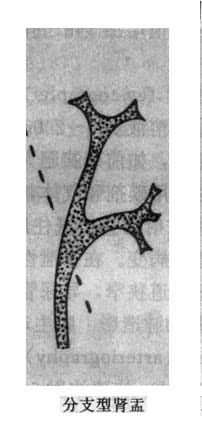

肾小盏分为体部及穹窿部。顶端由于乳头的突入而呈杯口状凹陷,边缘整齐,杯口的两缘为尖锐的小盏穹窿。肾小盏位于不同平面且指向不同方向(主要指向外方),如果肾小盏恰好面向X线束,成横断面投影(或称正位投影),则形成一个环状影或圆形致密影,勿误诊为结石。有时一个肾小盏可接受多个乳头伸入而表现为较大且不规则,多见于上、下盏。肾小盏体部较窄,又称为漏斗部。肾大盏边缘光滑整齐,略成长管状,可分三部:①顶端或尖部,与数个肾小盏相连;②峡部或颈部,即为和长管状部;③基底部,与肾盂相连。肾大小盏的形状和数目变异较多,有的粗短,有的细长,两侧肾盏的形状、数目亦常不同。但一般肾大盏常为3个。肾盂多位于第二腰椎水平,略呈三角形,上缘隆凸,下缘微凹,均光滑整齐。肾盂开头亦有较大变异,多呈喇叭状,少数可呈分支状,即肾盂几乎被两个长形肾大盏所代替。有的肾盂呈壶腹形,直接与肾小盏相连而没有肾大盏。这种肾盂勿误诊为肾盂扩大。肾盏和肾盂均有蠕动,有时其边缘可见到暂时性凹陷或狭窄,为蠕动波所成。肾血管有时亦在肾盏或肾盂边缘造成小的压迹,均属正常(图4-4-1)。

图4-4-1 正常肾盂肾盏不同形状(虚线状代表肾的内缘和肾门区)